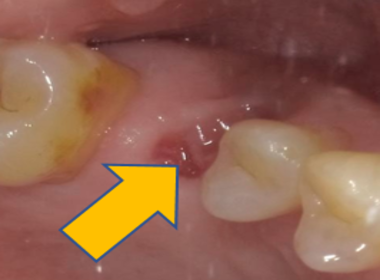

| 0313 #36#37 左下第一第二大臼齒 |

![]() |